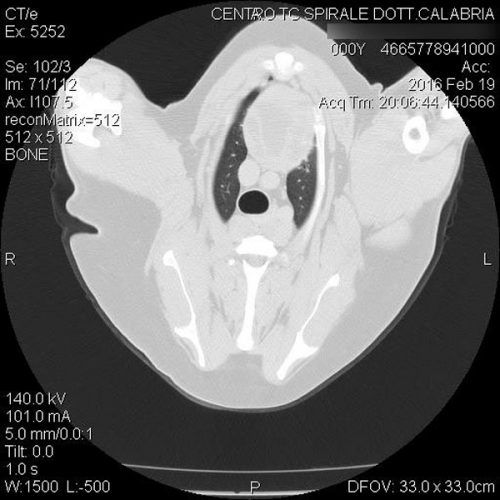

TC MULTISTRATO